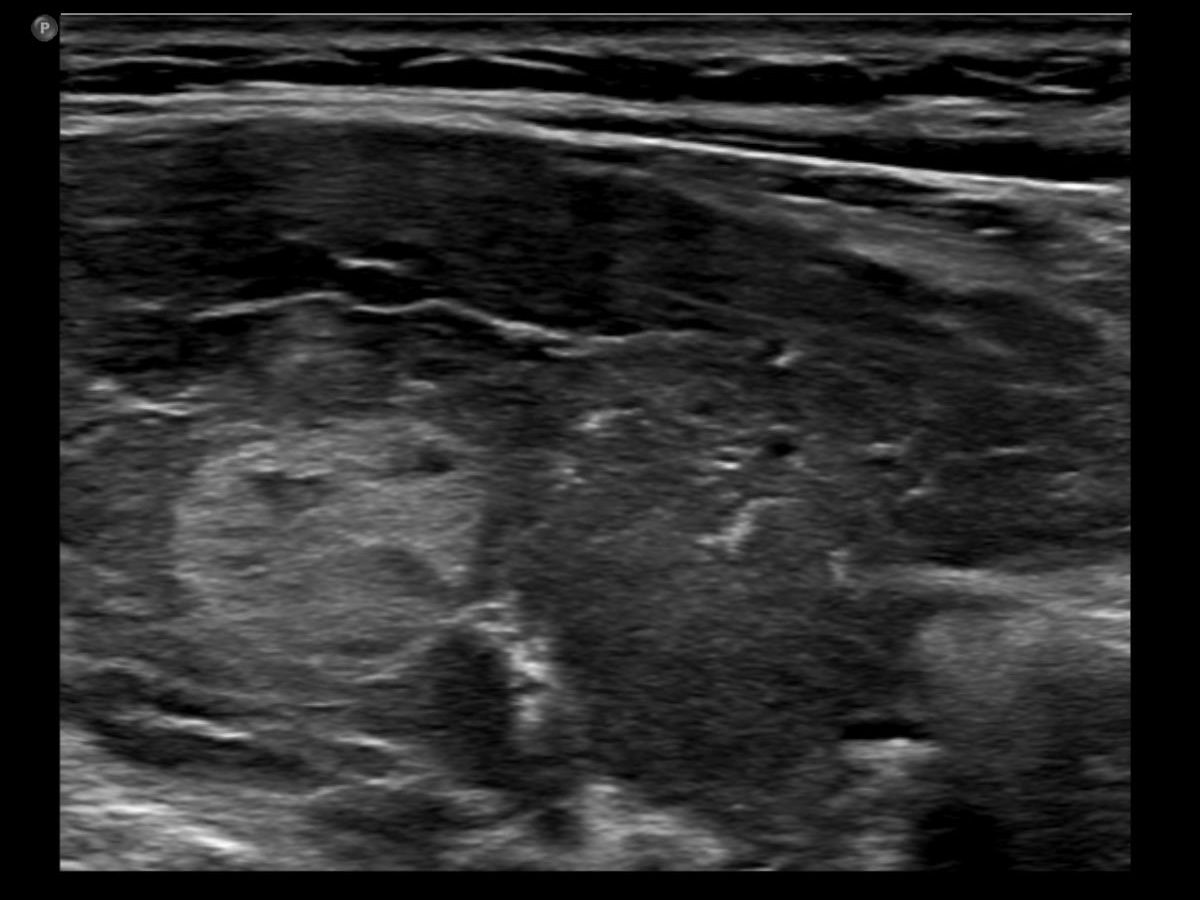

Comments.

- This case demonstrates the exception and not the rule. The echogenicity of a nodule almost always remains the same even over decades while in this patient the echogenicity has significantly changed two times within three years. The possible explanation is that the basic echo pattern of the extranodular thyroid and the vascularization influenced the pattern of the lesion.

- It is not evident whether the lesion in the right lobe is a single nodule with lobulated margins or a mass composed of multiple discrete lesions. In the former case the lobulation is pathological in the latter the undulation is not.